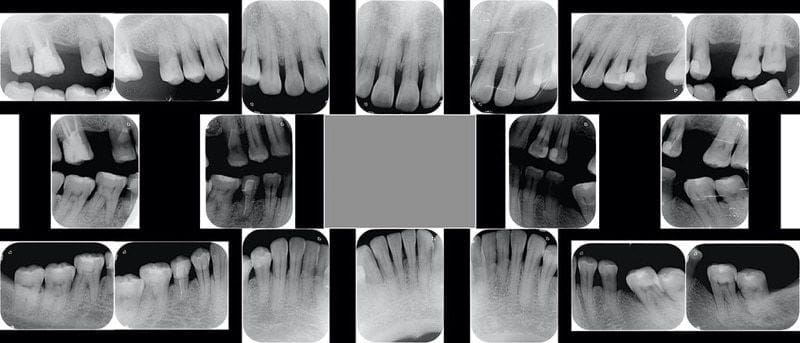

比照十年前的X光片,整體齒槽骨流失估計是10%,依照大部分牙周病的進展速度屬於中等(B級),但是在缺牙處旁的小臼齒區流失超過10%,破壞速度比較快(C級)。